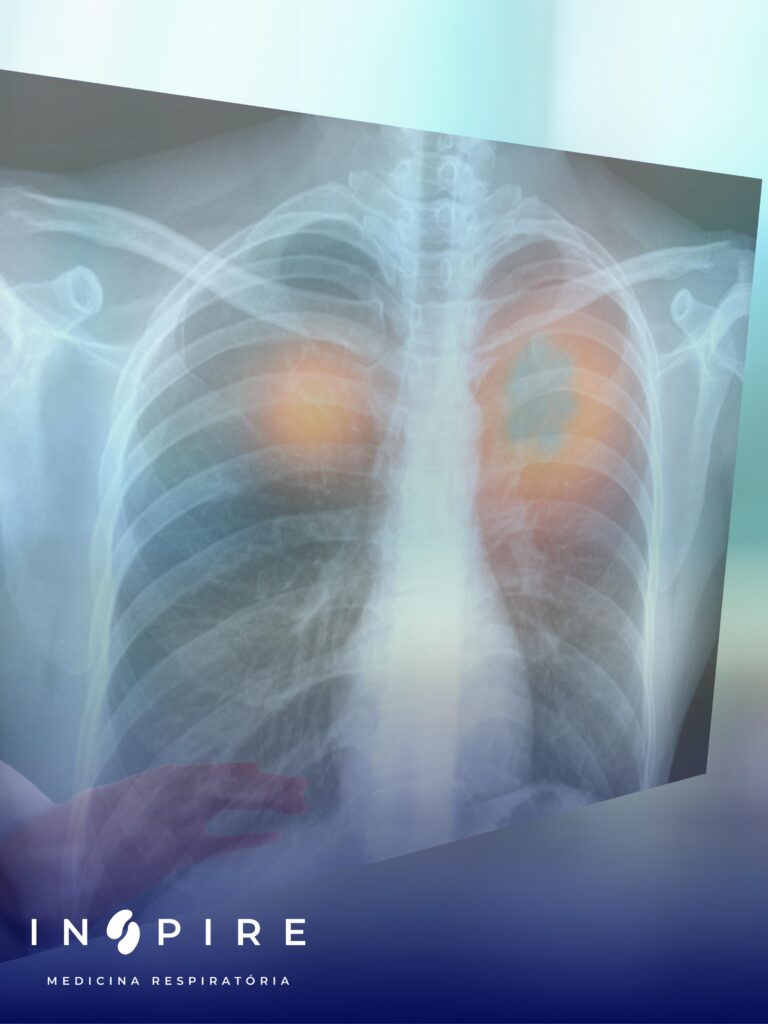

Cirurgia de Metástases Pulmonares: Quando Indicar e Quais os Resultados

As metástases pulmonares são tumores que se originam em outros órgãos e se disseminam para os pulmões. Esse fenômeno é relativamente comum, já que o pulmão é um dos principais locais de disseminação de células cancerígenas devido à sua extensa rede de vasos sanguíneos e linfáticos. Embora as metástases representem uma condição oncológica avançada, em […]